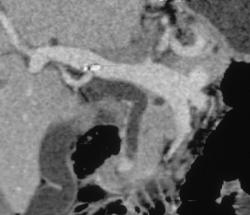

Pancreatic Cancer